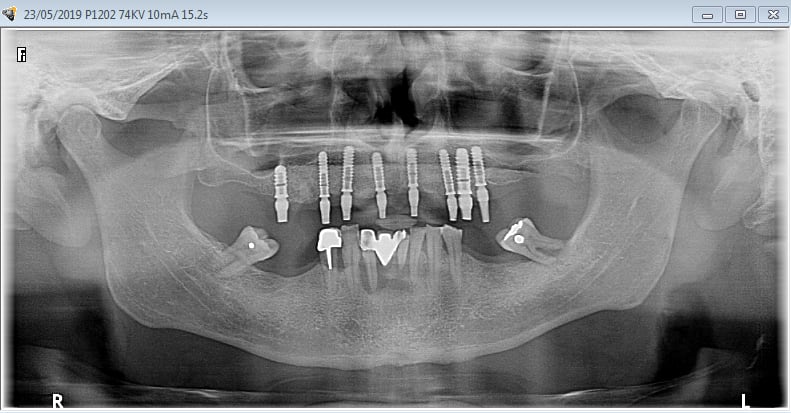

La vidéo présente à partir des plans de traitements, des chirurgies de beotien , des dispositifs médicaux sur mesure positdental et positguide la mise en charge immédiate post-extractionnelle d’un bridge provisoire à armature métal en prothèse fixe sur implants cône morse donc sans vis de maintien. Une question est émise « comment obtient-on ce résultat ? ». Une partie des réponses comme la prédictibilité, la reproductibilité peuvent y être déduite pour d’autre il faudra la bonté de beotien de faire partager les résultats clinique.il nous fait la générosité de poster la phase cicatriciel à 7 jours et des photos de la chirurgie sur un cas.

Vous regardez un cas de mci et ne voyez que l’implant sur 9 (je ne parle pas des derniers qui n’ont que quelques jours) qui posé il y a 4 ans lors d’un sinus lift latéral ne va pas bien, et de 2 (8) qu’un 3ème année pourrait enlever.

Ce patient arrivant aujourd’hui en consultation avec la pano initiale, je dirais aussi que mon protocole est nul et il n’a que 4 ans.

Je viens de relire ce sujet d'il y a maintenant 6 ans.

Je viens de revoir au cabinet un des 3 cas, car la céramique de la 25 était fracturée.

J'ai pris une photo (iphone) avec le bridge déposé avant de mettre temporairement le bridge coping de Posit. Pas la peine de commenter le bas je n'en suis pas responsable.